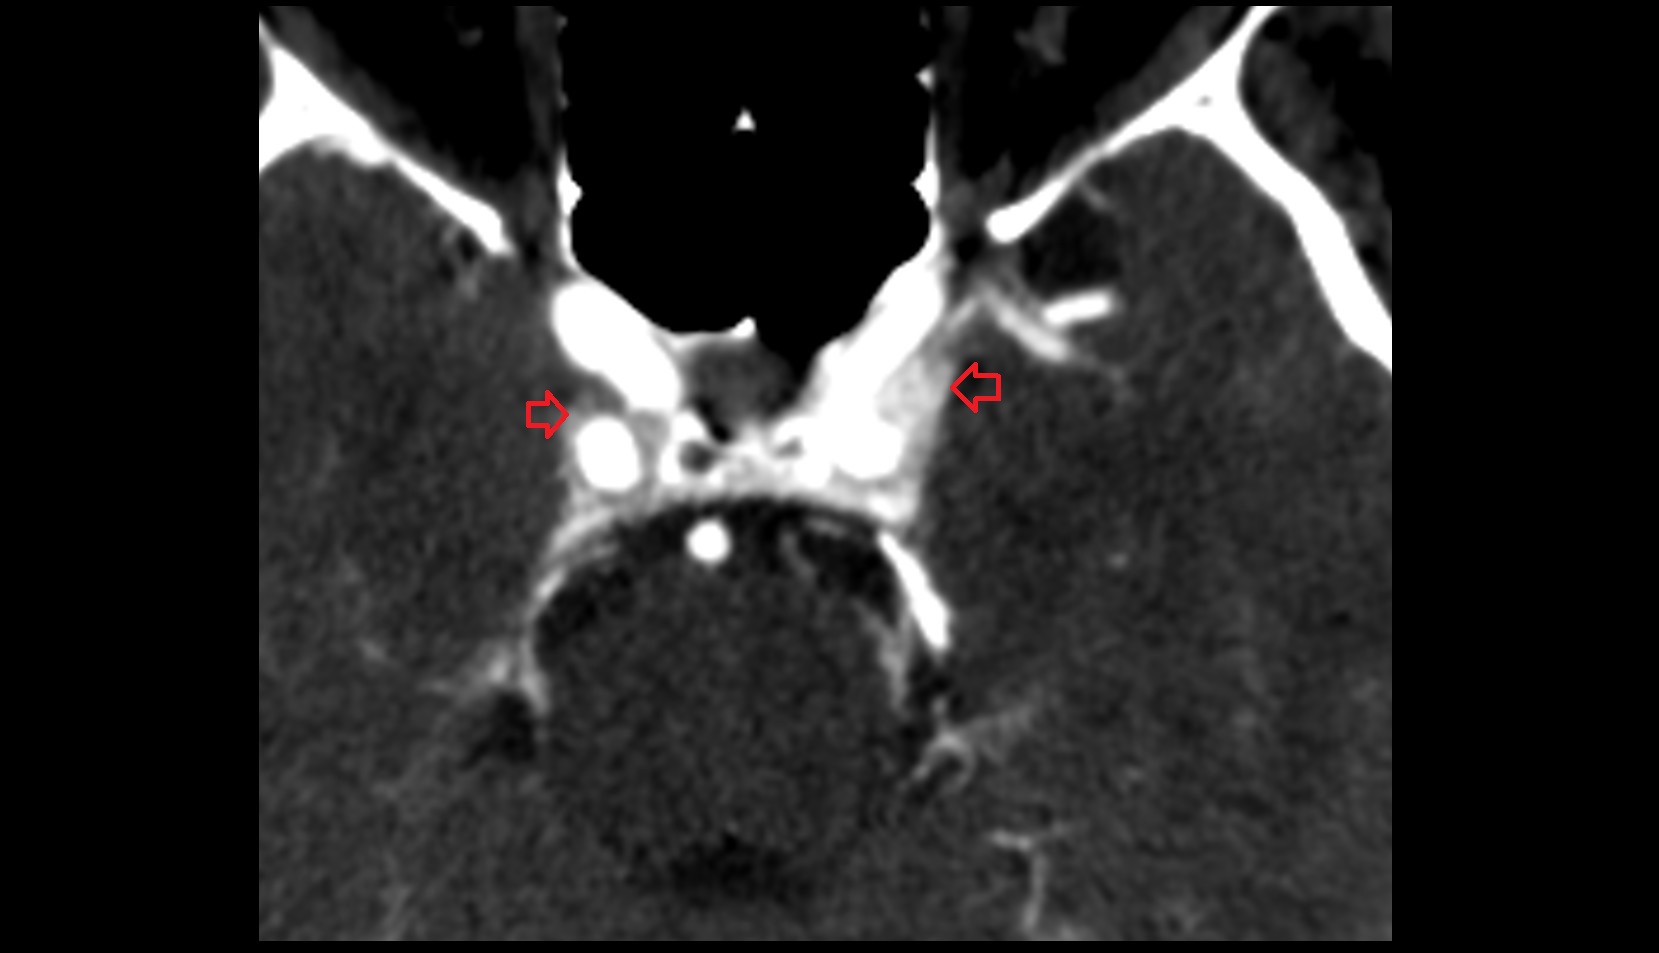

- Exit foramina